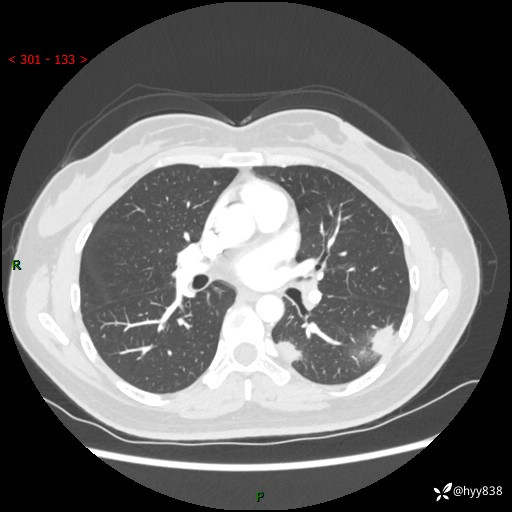

36岁/女,左侧下胸部阵发性疼痛2周,乏力1周。精彩无限,等你来诊---结果公布~

【患者信息】:36岁/女

【主诉】:左侧下胸部阵发性疼痛2周,乏力1周

【现病史及既往史】:患者自诉2周前饮酒后出现左侧下胸部阵发性疼痛,不随呼吸改变,无咳嗽咳痰、头晕头痛、咳血、呼吸困难等不适,于当地第一人民医院查胸部CT提示肺部感染,随后前往我院门诊给予抗感染(左氧氟沙星)治疗1周,自诉胸痛较前好转,感乏力、头晕,偶尔干咳,无咳痰,无发热、畏寒、胸闷、咯血、四肢酸痛、腹泻、腹痛等不适,门诊复查胸部CT提示:左肺下叶感染,病灶较前增加增大,遂以“肺部感染”收入我科。 起病以来,患者精神、饮食、睡眠可,大小便正常,体力体重无明显变化。

【检查】:胸部CT增强(外院平扫)